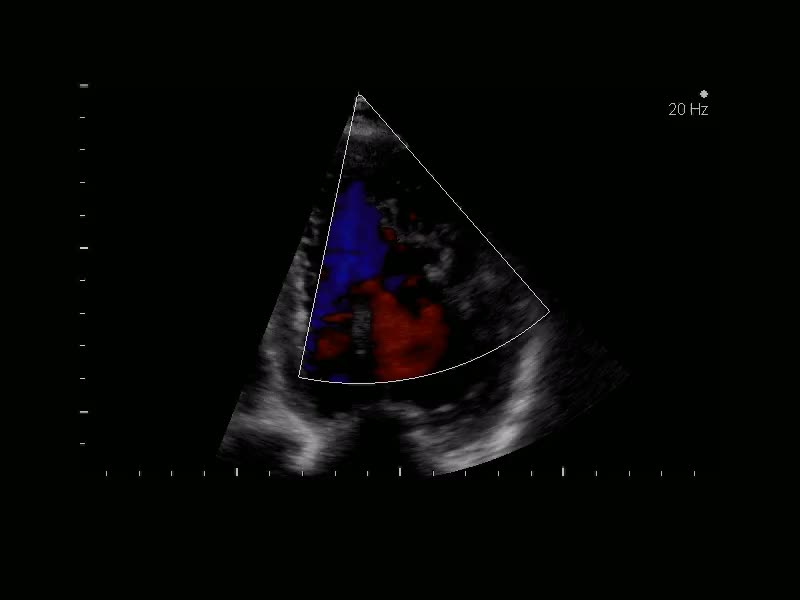

Prolasso mitralico con IM severa

Eleonora Zenoni